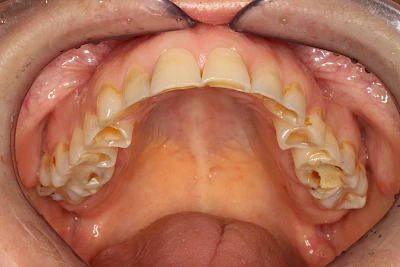

Auswaschung (Erosion) dagegen ist eine Verschleißerscheinung der Zähne aufgrund von immer wiederkehrenden Säureangriffen durch die Nahrung, verstärkt zum Beispiel durch den Genuss säurehaltiger Getränke oder Speisen. Auch bei Menschen mit einer Essstörung (z. B. Bulimie) können die Zähne durch die Magensäure ausgewaschen erscheinen.

Keilförmiger Defekt

Eine Sonderform sind sogenannte keilförmige Defekte im Bereich der Zahnhälse. Hier geht man davon aus, dass Knirschen und Pressen in Kombination mit falschen Putzgewohnheiten (zu hoher Putzdruck, Verwendung von Zahnpasta mit hohen Abrasionswerten) eine Rolle spielen.